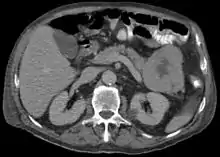

ACC are typically large, up to 10 cm, and soft compared to pancreatic adenocarcinoma, lacking its dense stroma. They can arise in any part of the pancreas.[2]

Diagnosis

Light microscopy of an acinar cell carcinoma biopsy typically shows granular appearance.[5] Immunohistochemistry is usually positive for trypsin, chymotrypsin and lipase.[5] On genetic testing, altered genes/proteins are typically found for p53, SMAD4, APC, ARID1A and GNAS.[5]